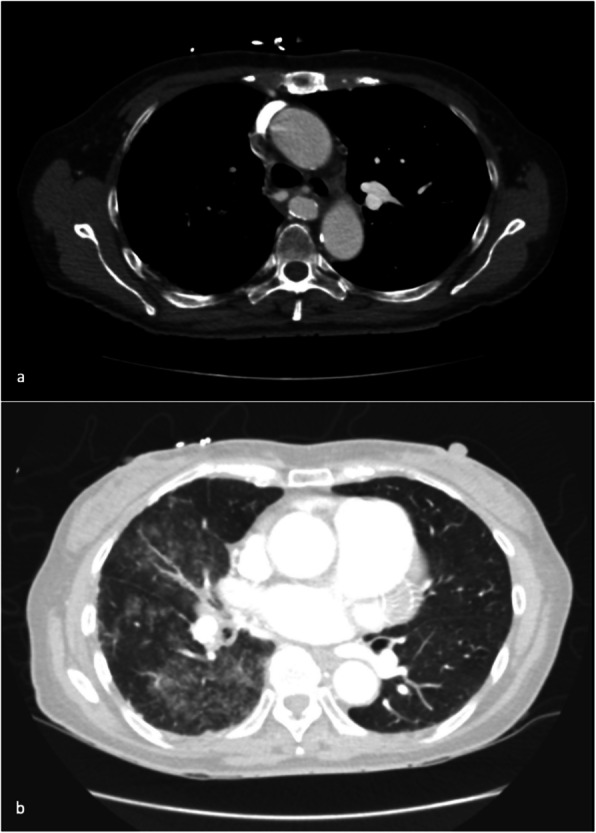

{"title":"肺动脉近端中断伴全身支气管/肋间动脉瘤形成:1例报告。","authors":"Runlin Yang, Robert Ng, Albert Goh, Richard Pow","doi":"10.1186/s42155-025-00519-0","DOIUrl":null,"url":null,"abstract":"<p><p>Proximal Interruption of the Pulmonary Artery (PIPA) is a rare congenital condition with an incidence of 1 in 200,000-300,000 individuals. We report the case of a 67-year-old woman with PIPA who presented with massive haemoptysis. Imaging revealed a small calibre right main pulmonary artery, absence of upper/middle lobe pulmonary arteries, and tortuous right systemic collateral arteries. A multidisciplinary meeting favoured bronchial artery embolisation over right pneumonectomy, due to the bleeding risk associated with extensive transpleural systemic collateral arteries. The patient underwent two staged bronchial artery embolisation and remained free of haemoptysis at the most recent 13-month follow-up. This case highlights the potential for bronchial artery embolisation to serve as a first-line treatment in managing PIPA, as a less invasive alternative to surgery.</p>","PeriodicalId":52351,"journal":{"name":"CVIR Endovascular","volume":"8 1","pages":"60"},"PeriodicalIF":1.5000,"publicationDate":"2025-08-01","publicationTypes":"Journal Article","fieldsOfStudy":null,"isOpenAccess":false,"openAccessPdf":"https://www.ncbi.nlm.nih.gov/pmc/articles/PMC12316662/pdf/","citationCount":"0","resultStr":"{\"title\":\"Proximal interruption of the pulmonary artery with systemic bronchial/intercostal aneurysm formation: a case report.\",\"authors\":\"Runlin Yang, Robert Ng, Albert Goh, Richard Pow\",\"doi\":\"10.1186/s42155-025-00519-0\",\"DOIUrl\":null,\"url\":null,\"abstract\":\"<p><p>Proximal Interruption of the Pulmonary Artery (PIPA) is a rare congenital condition with an incidence of 1 in 200,000-300,000 individuals. We report the case of a 67-year-old woman with PIPA who presented with massive haemoptysis. Imaging revealed a small calibre right main pulmonary artery, absence of upper/middle lobe pulmonary arteries, and tortuous right systemic collateral arteries. A multidisciplinary meeting favoured bronchial artery embolisation over right pneumonectomy, due to the bleeding risk associated with extensive transpleural systemic collateral arteries. The patient underwent two staged bronchial artery embolisation and remained free of haemoptysis at the most recent 13-month follow-up. This case highlights the potential for bronchial artery embolisation to serve as a first-line treatment in managing PIPA, as a less invasive alternative to surgery.</p>\",\"PeriodicalId\":52351,\"journal\":{\"name\":\"CVIR Endovascular\",\"volume\":\"8 1\",\"pages\":\"60\"},\"PeriodicalIF\":1.5000,\"publicationDate\":\"2025-08-01\",\"publicationTypes\":\"Journal Article\",\"fieldsOfStudy\":null,\"isOpenAccess\":false,\"openAccessPdf\":\"https://www.ncbi.nlm.nih.gov/pmc/articles/PMC12316662/pdf/\",\"citationCount\":\"0\",\"resultStr\":null,\"platform\":\"Semanticscholar\",\"paperid\":null,\"PeriodicalName\":\"CVIR Endovascular\",\"FirstCategoryId\":\"1085\",\"ListUrlMain\":\"https://doi.org/10.1186/s42155-025-00519-0\",\"RegionNum\":0,\"RegionCategory\":null,\"ArticlePicture\":[],\"TitleCN\":null,\"AbstractTextCN\":null,\"PMCID\":null,\"EPubDate\":\"\",\"PubModel\":\"\",\"JCR\":\"Q3\",\"JCRName\":\"CARDIAC & CARDIOVASCULAR SYSTEMS\",\"Score\":null,\"Total\":0}","platform":"Semanticscholar","paperid":null,"PeriodicalName":"CVIR Endovascular","FirstCategoryId":"1085","ListUrlMain":"https://doi.org/10.1186/s42155-025-00519-0","RegionNum":0,"RegionCategory":null,"ArticlePicture":[],"TitleCN":null,"AbstractTextCN":null,"PMCID":null,"EPubDate":"","PubModel":"","JCR":"Q3","JCRName":"CARDIAC & CARDIOVASCULAR SYSTEMS","Score":null,"Total":0}

近端肺动脉中断(PIPA)是一种罕见的先天性疾病,发病率为20 -30万分之一。我们报告的情况下,67岁的妇女PIPA谁提出了大量咯血。影像学显示右肺主干小口径,肺上/中叶动脉缺失,右全身侧支动脉迂曲。一个多学科会议倾向于支气管动脉栓塞而不是右侧肺切除术,因为出血风险与广泛的经胸膜全身侧支动脉相关。患者接受了两次分阶段支气管动脉栓塞,在最近13个月的随访中仍无咯血。该病例强调了支气管动脉栓塞作为治疗PIPA的一线治疗方法的潜力,作为一种侵入性较小的手术替代方法。

Proximal Interruption of the Pulmonary Artery (PIPA) is a rare congenital condition with an incidence of 1 in 200,000-300,000 individuals. We report the case of a 67-year-old woman with PIPA who presented with massive haemoptysis. Imaging revealed a small calibre right main pulmonary artery, absence of upper/middle lobe pulmonary arteries, and tortuous right systemic collateral arteries. A multidisciplinary meeting favoured bronchial artery embolisation over right pneumonectomy, due to the bleeding risk associated with extensive transpleural systemic collateral arteries. The patient underwent two staged bronchial artery embolisation and remained free of haemoptysis at the most recent 13-month follow-up. This case highlights the potential for bronchial artery embolisation to serve as a first-line treatment in managing PIPA, as a less invasive alternative to surgery.